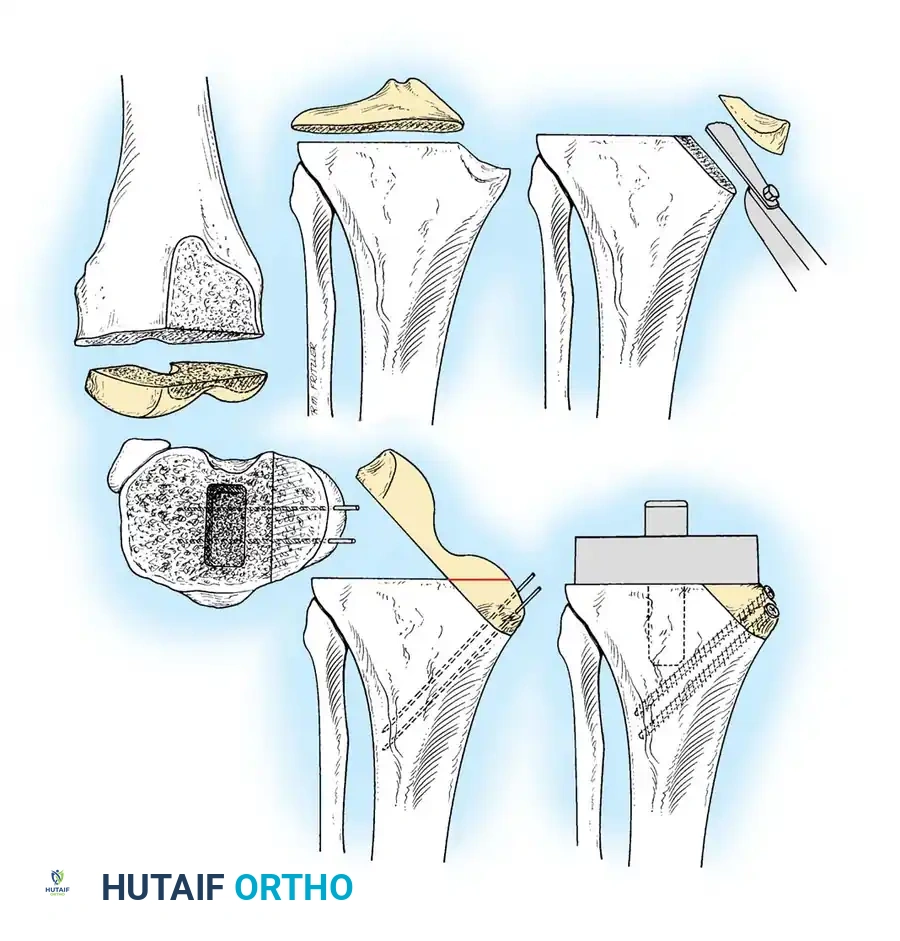

The distal femoral cut sets the extension gap and determines the coronal alignment of the femoral component.

- Make the distal femoral cut at a valgus angle (usually 5 to 7 degrees) perpendicular to the predetermined mechanical axis of the femur. This is typically achieved using an intramedullary alignment guide.

- The thickness of the bone removed should generally equal the thickness of the distal flange of the femoral component (typically 9 to 10 mm).

- If a significant preoperative flexion contracture is present, removing an additional 2 to 3 mm of distal femoral bone will widen the extension gap, aiding in contracture correction.

Femoral Chamfer Cuts and Intercondylar Preparation

Once sizing and rotation are established, the cutting block is pinned in place.

- Complete the distal femoral preparation by making the anterior, posterior, and chamfer cuts.

- If a PCL-retaining (CR) prosthesis is used, the intercondylar notch is left intact.

- If a PCL-substituting (PS) design is chosen, an intercondylar box cut is performed to accommodate the housing for the post-and-cam mechanism.

Proximal Tibial Preparation

The goal of the tibial resection is to create a flat, stable platform perpendicular to the mechanical axis of the tibia in the coronal plane, while recreating the appropriate posterior slope in the sagittal plane.

- Cut the tibia perpendicular to its mechanical axis. Extramedullary alignment guides are most commonly used, referencing the center of the tibial tubercle proximally and the center of the talus distally.

- Incorporate 0 to 5 degrees of posterior slope, depending on the implant design and the patient's native anatomy.

- Cruciate-Retaining (CR) implants typically require more posterior slope (3–7 degrees) to prevent PCL tightness in flexion.

- Posterior-Stabilized (PS) implants generally require less slope (0–3 degrees) to prevent early impingement of the tibial post against the femoral cam.

- The depth of resection is typically 8 to 10 mm from the intact lateral tibial plateau, ensuring adequate thickness for the polyethylene insert without excessively raising the joint line.